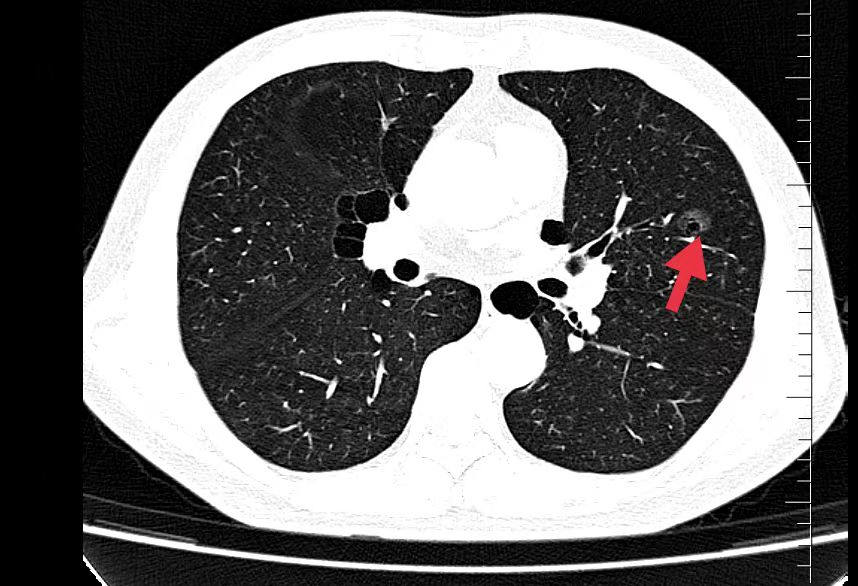

02、**男士,60岁

于2023年7月24日在邯郸仁泰东区体检,低剂量薄层CT扫描提示:左肺舌叶磨玻璃结节,大小约17mm。2023年7月25日首次回访,通知客户到三甲医院进一步检查和治疗。2023年8月30日跟踪回访,客户告知到邯郸市中心医院进一步检查,建议手术治疗,客户到北京肿瘤医院再一次检查同样建议手术治疗,已在北京肿瘤医院住院准备手术治疗。